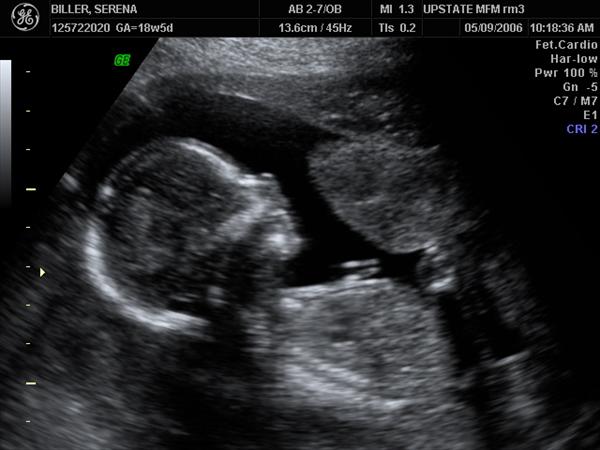

Photo Number 148